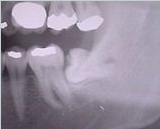

2. 매복니: 사랑니가 잇몸에서 완전히 나오지 않으면 매복이 됩니다.

주변에 사랑니 뽑으면서 고생한 사람들이 많아 후기보고 별점 보고 가보았습니다.선생님께서 구강악안면외과 교수님 출신이라고 적혀 있었는데 정말 사랑니만 뽑는 병원이었습니다.요즘 치과도 포화상태라 교정해야 수익이 난다 들었는데 사랑니가 치과계의 블루오션이었네요.저희 딸아이는 아랫니 양쪽다 누워있는 매복이라 통증이 있는 쪽을 발치를 했습니다.20분 정도 걸린다고 했는데 10분도 안되어 다 끝났더군요.같은 매복니였던 아이아빠는 한 시간 동안 걸려서 깨서 뽑았었는데 감동이었습니다.사랑니 뽑으실분들은 근처 검색해서 보고 가세요.저는 비용이 아깝지 않았습니다.그래서 오늘은 사랑니에 대해 알아보고자 합니다.